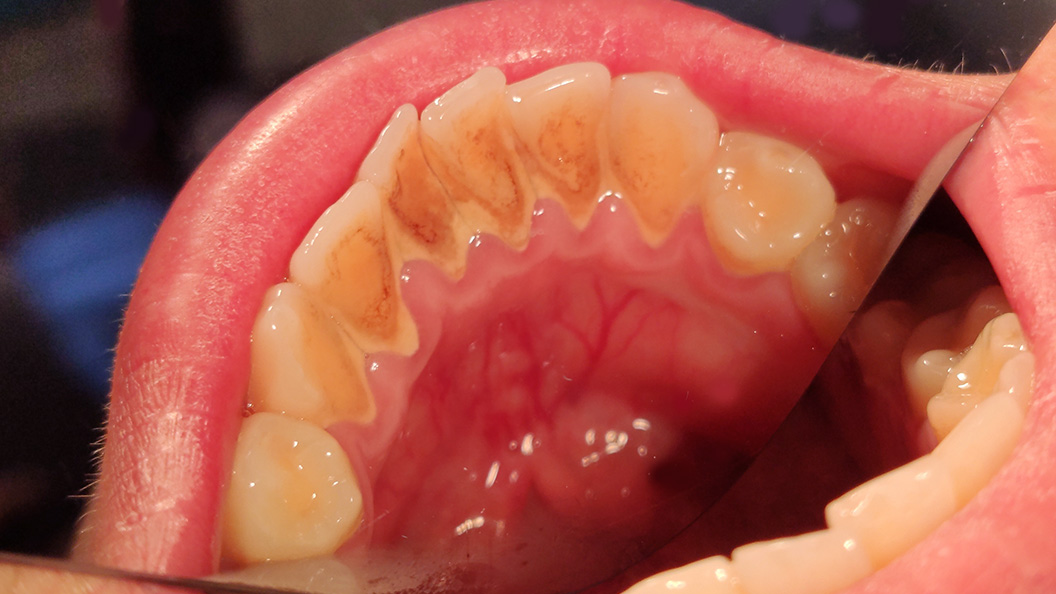

К нам в клинику обратился пациент с жалобами на наличие зубных отложений в области 4-х сегментов и кровоточивость во время чистки зубов.

На момент осмотра были обнаружены наддесневые зубные отложения, десна отёчна и кровоточила при зондировании. Нашим специалистом Григорьевым Петром Игоревичем была назначена профессиональная гигиена полости рта

- снятие твёрдых отложений с помощью ультразвукового аппарата;

- чистка зубов от пигментированного налёта пастой "Detartrine Z";